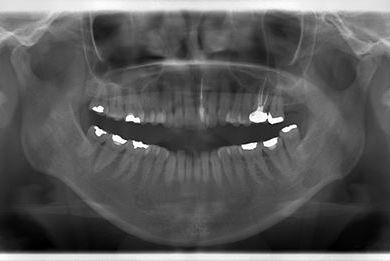

セラミックの症例写真 SHINBI

セラミック治療+ラミネートベニア治療

| 主訴 | 虫歯を白い詰め物で治療したい。全体的に歯の色が気になるので、ホワイトニングをしたい。ホワイトニングの効果がなければ、セラミック治療を受けたい。 | ||||||||||||||||||||||||||||||||

| 治療方針 | セラミック治療にて、審美的回復を行う。 | ||||||||||||||||||||||||||||||||

| 治療内容 | ジルコニアオールセラミッククラウン1本(オールセラミック用土台1本)、オールセラミッククラウン9本(オールセラミック用土台1本)、オールセラミックラミネートベニア11本 | ||||||||||||||||||||||||||||||||

| 総治療費 | 2,893,275円 | ||||||||||||||||||||||||||||||||

| 治療期間 | 10ヶ月 |